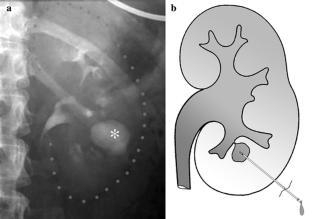

Fig. 1